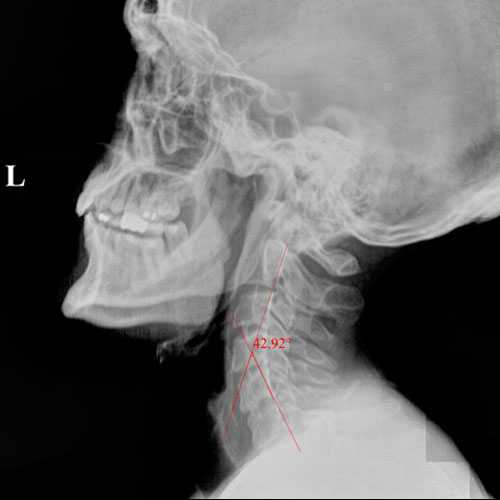

In this case, initial cervical spine X-rays revealed a significant loss of normal neck curvature, a condition that places excessive strain on the spine and nervous system. When the cervical curve is reduced, the head shifts forward, increasing stress on spinal joints, discs, and nerves — often leading to chronic neck pain, headaches, migraines, and neurological symptoms.

Before Chiropractic Treatment: The patient’s X-rays showed a flattened cervical curve, meaning the neck was no longer supporting the head in its ideal position. This type of misalignment is commonly linked to long-term spinal degeneration, nerve irritation, and persistent symptoms that don’t resolve with medication alone.

When spinal structure is compromised, the body is forced to compensate — and over time, those compensations break down.